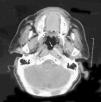

Acta Otorrinolaringológica Española Arteria carótida interna paralela a la base del cráneo

Arteria carótida interna paralela a la base del cráneo

Internal carotid artery parallel to the skull base